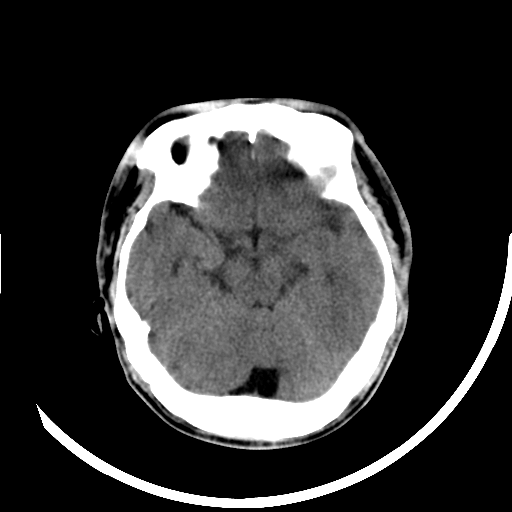

本帖最后由 cefcmj 于 2015-6-16 20:53 编辑 神志不清,检查。胸部平片示双肺见模糊阴影。现请求会诊,谢谢!!

转移可能

脑梗赛可能,建议mR增强

支持脑梗塞。

梗塞 结节硬化

梗塞可能,建议增强扫描。

转移可能,建议强化